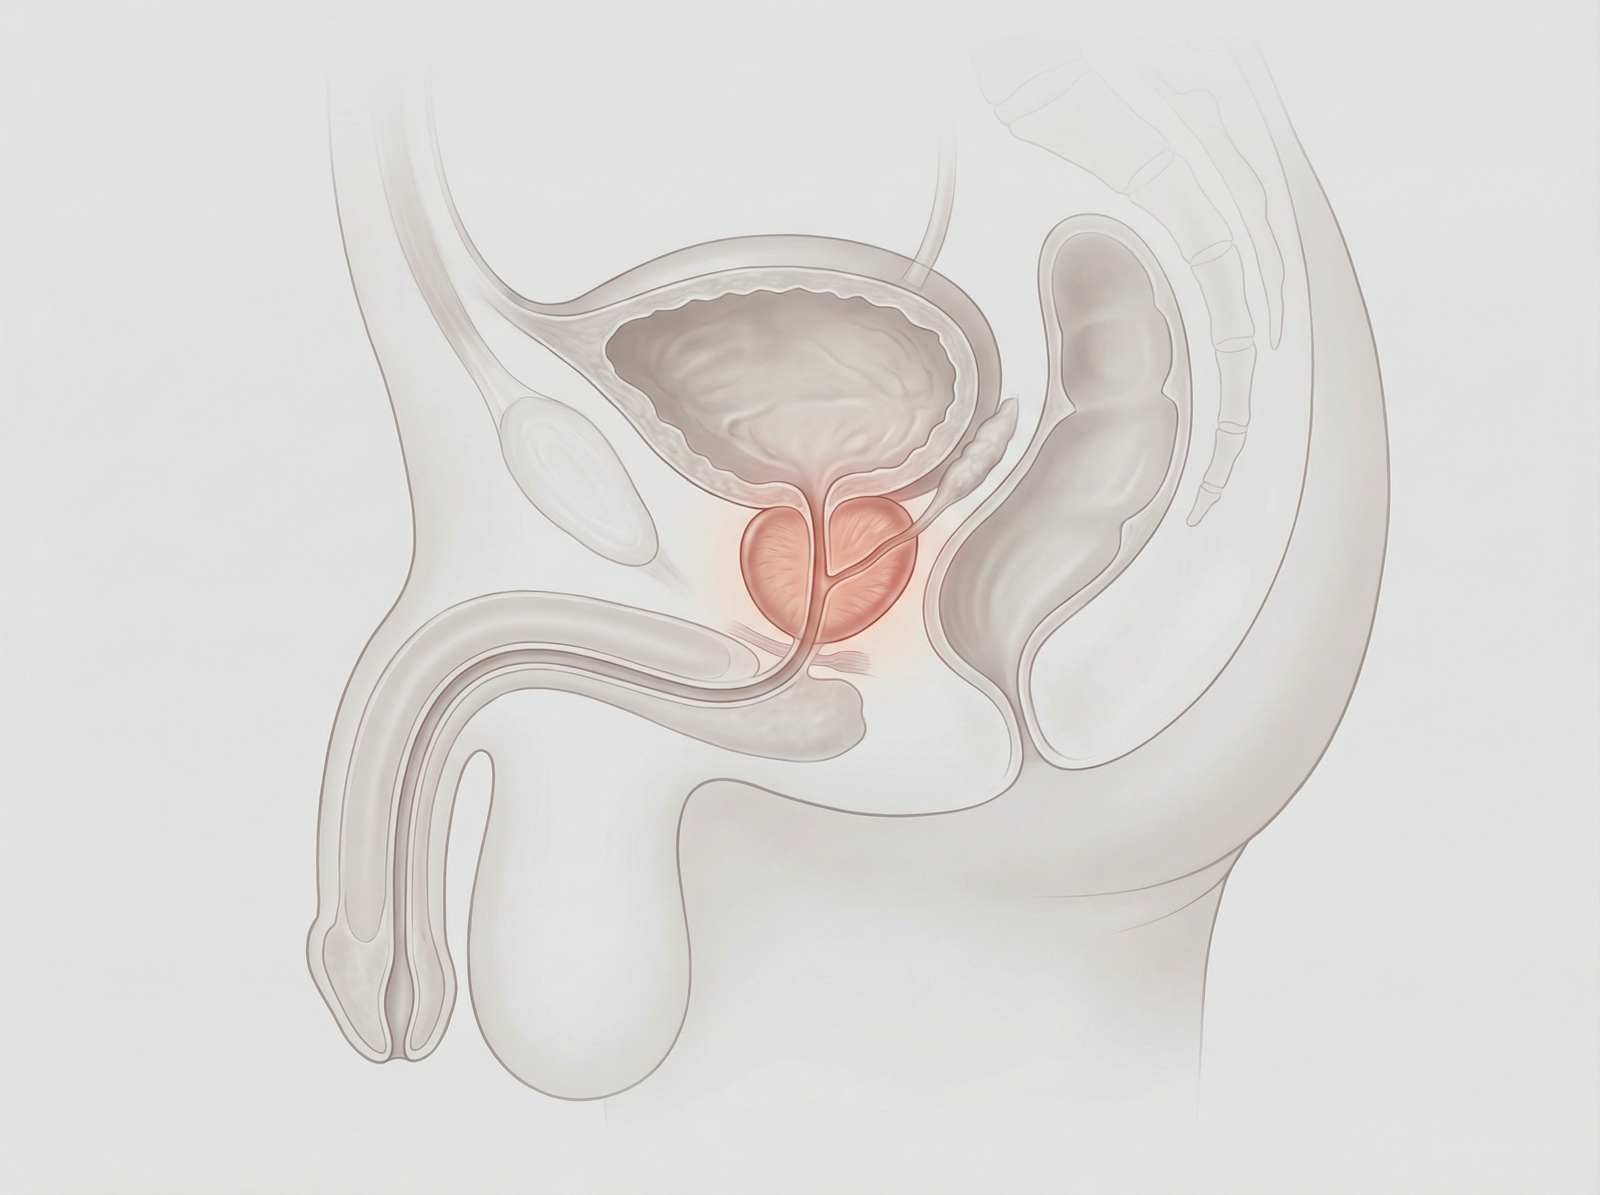

Enucleazione laser a fibra di tulio della prostata (ThuFLEP). Tecnica avanzata e mininvasiva per il trattamento dell’ipertrofia prostatica benigna, che consente la rimozione precisa del tessuto in eccesso con minimo sanguinamento. Recupero più rapido, maggiore sicurezza e miglioramento significativo dei sintomi urinari, per una migliore qualità della vita.

Hai problemi ad urinare a causa dell’ingrossamento della prostata? Presso la clinica Fabjan in Slovenia eseguiamo l’enucleazione laser della prostata con il laser a fibra di Thulium – ThuFLEP.